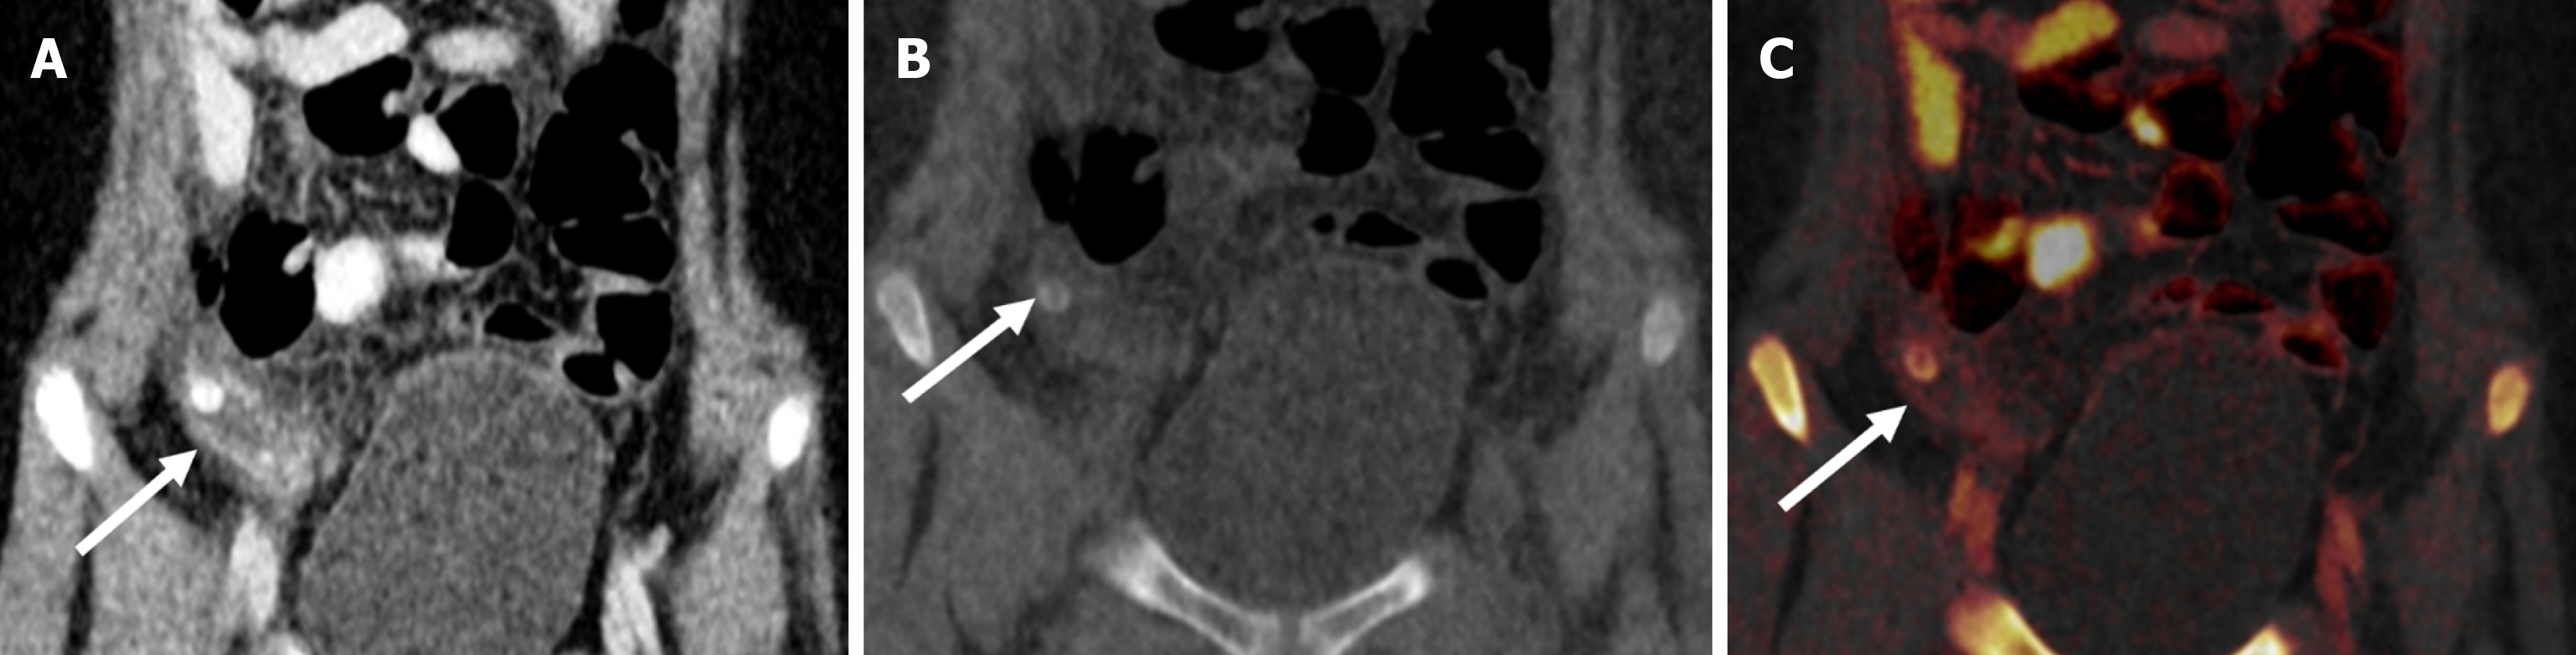

Figure 11 A 10-year-old female with acute pain in the right iliac fossa.

A: Blended dual-energy contrast-enhanced coronal image showed circum ferential homogenously enhancing mural thickening involving the wall of the appendix (arrow), which was dilated and fluid-filled, suggestive of acute appendicitis; B: There was also the presence of an oval-shaped hyperdensity (arrow) within its lumen on virtual non-contrast image, suggestive of an appendicolith; C: The iodine overlay map showed high iodine uptake in its wall (arrow), representing the hyperemia associated with active inflammation.